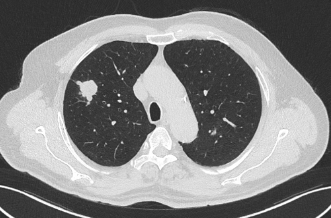

近日,昭通市中医医院呼吸与危重症医学科二科成功为一名合并多种基础疾病的61岁肺癌患者实施了昭通首例经口支气管镜超声(EBUS)引导下肺癌冷冻消融术。该患者因“反复咳嗽、咳痰1年,确诊右肺鳞癌2月余”入院。胸部增强CT显示其右肺上叶存在两个高危结节(Lung-RADs 4X类),同时合并慢性支气管炎伴肺气肿、肺炎、冠心病(支架术后)、肺大疱、肺不张等疾患。

术前患者CT